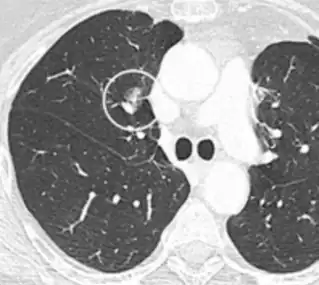

- In case of subsolid nodules, being part solid has a higher risk of cancer than being purely ground glass opacity.

Part solid nodule.[9]

Ground glass opacity nodule.[9]